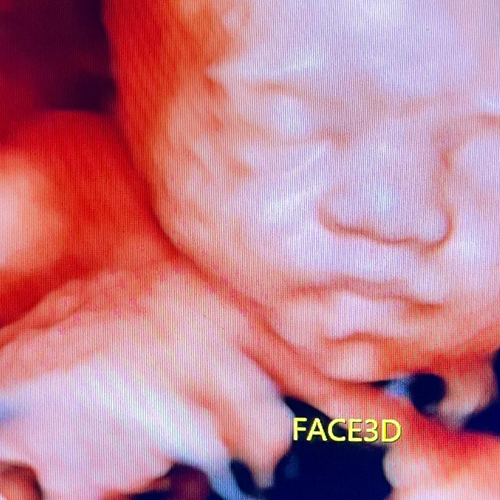

Best Scanning Center In Nakodar